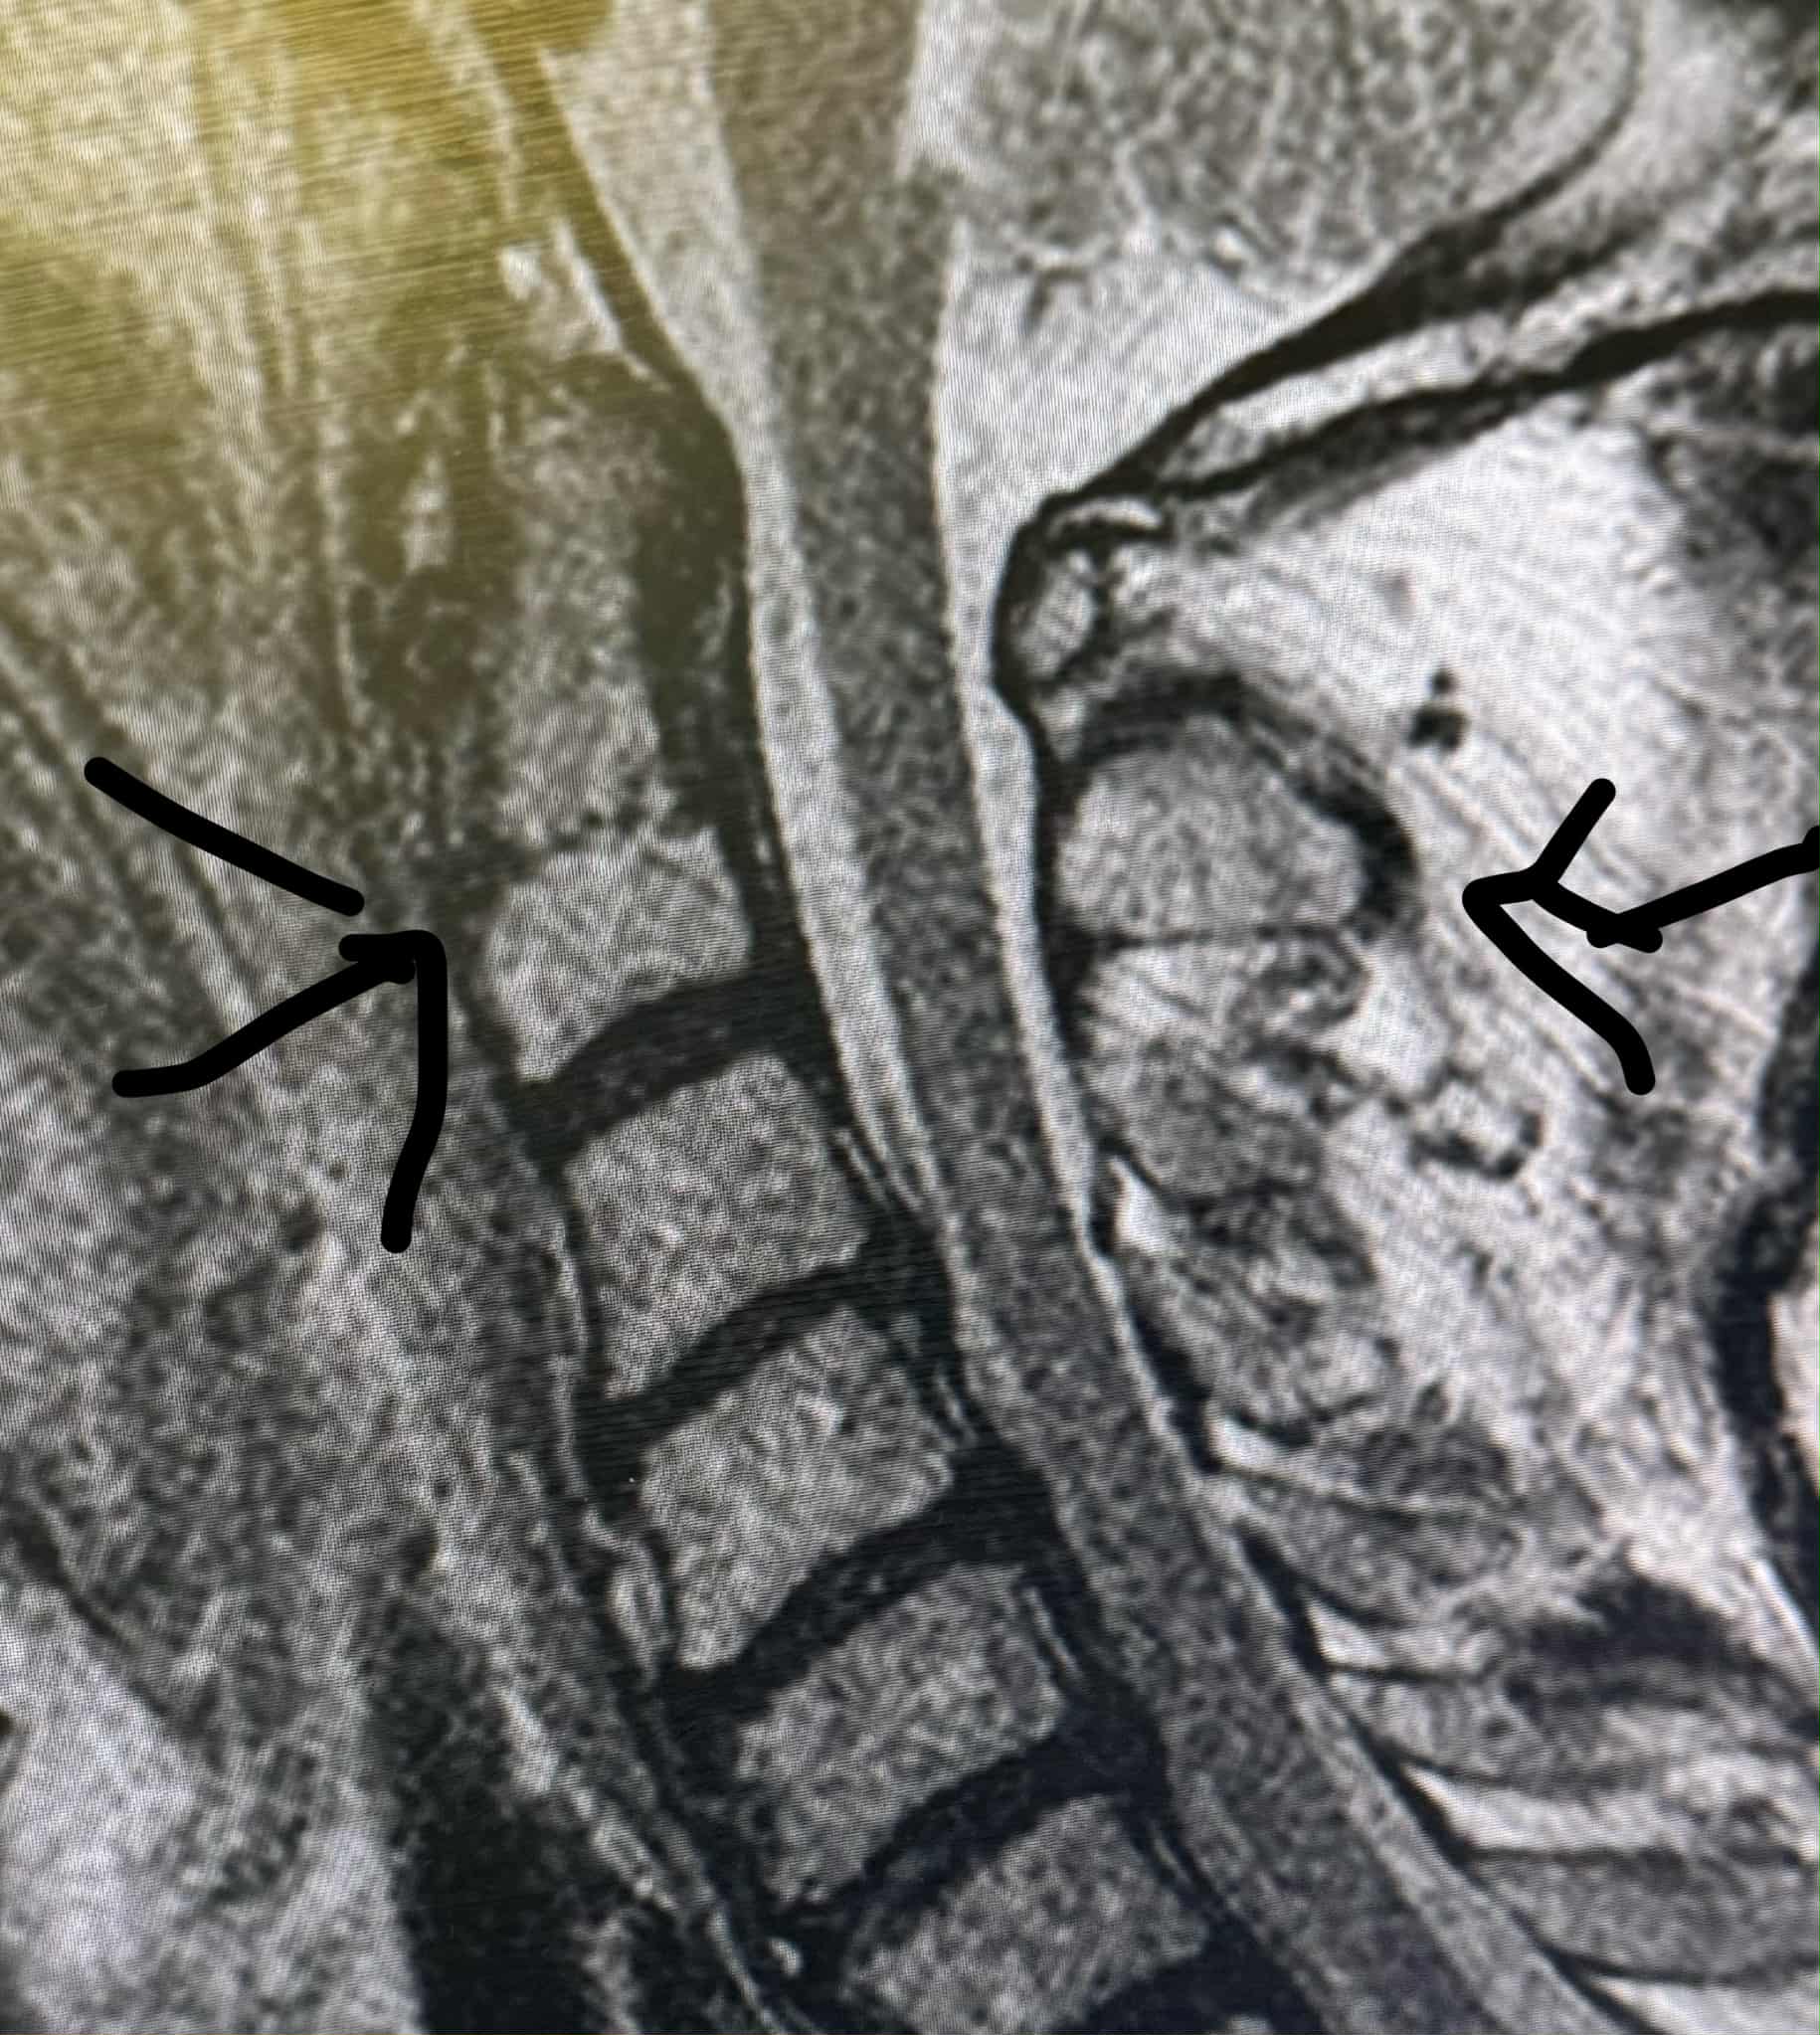

- A broken neck in two places

A broken neck in two places.